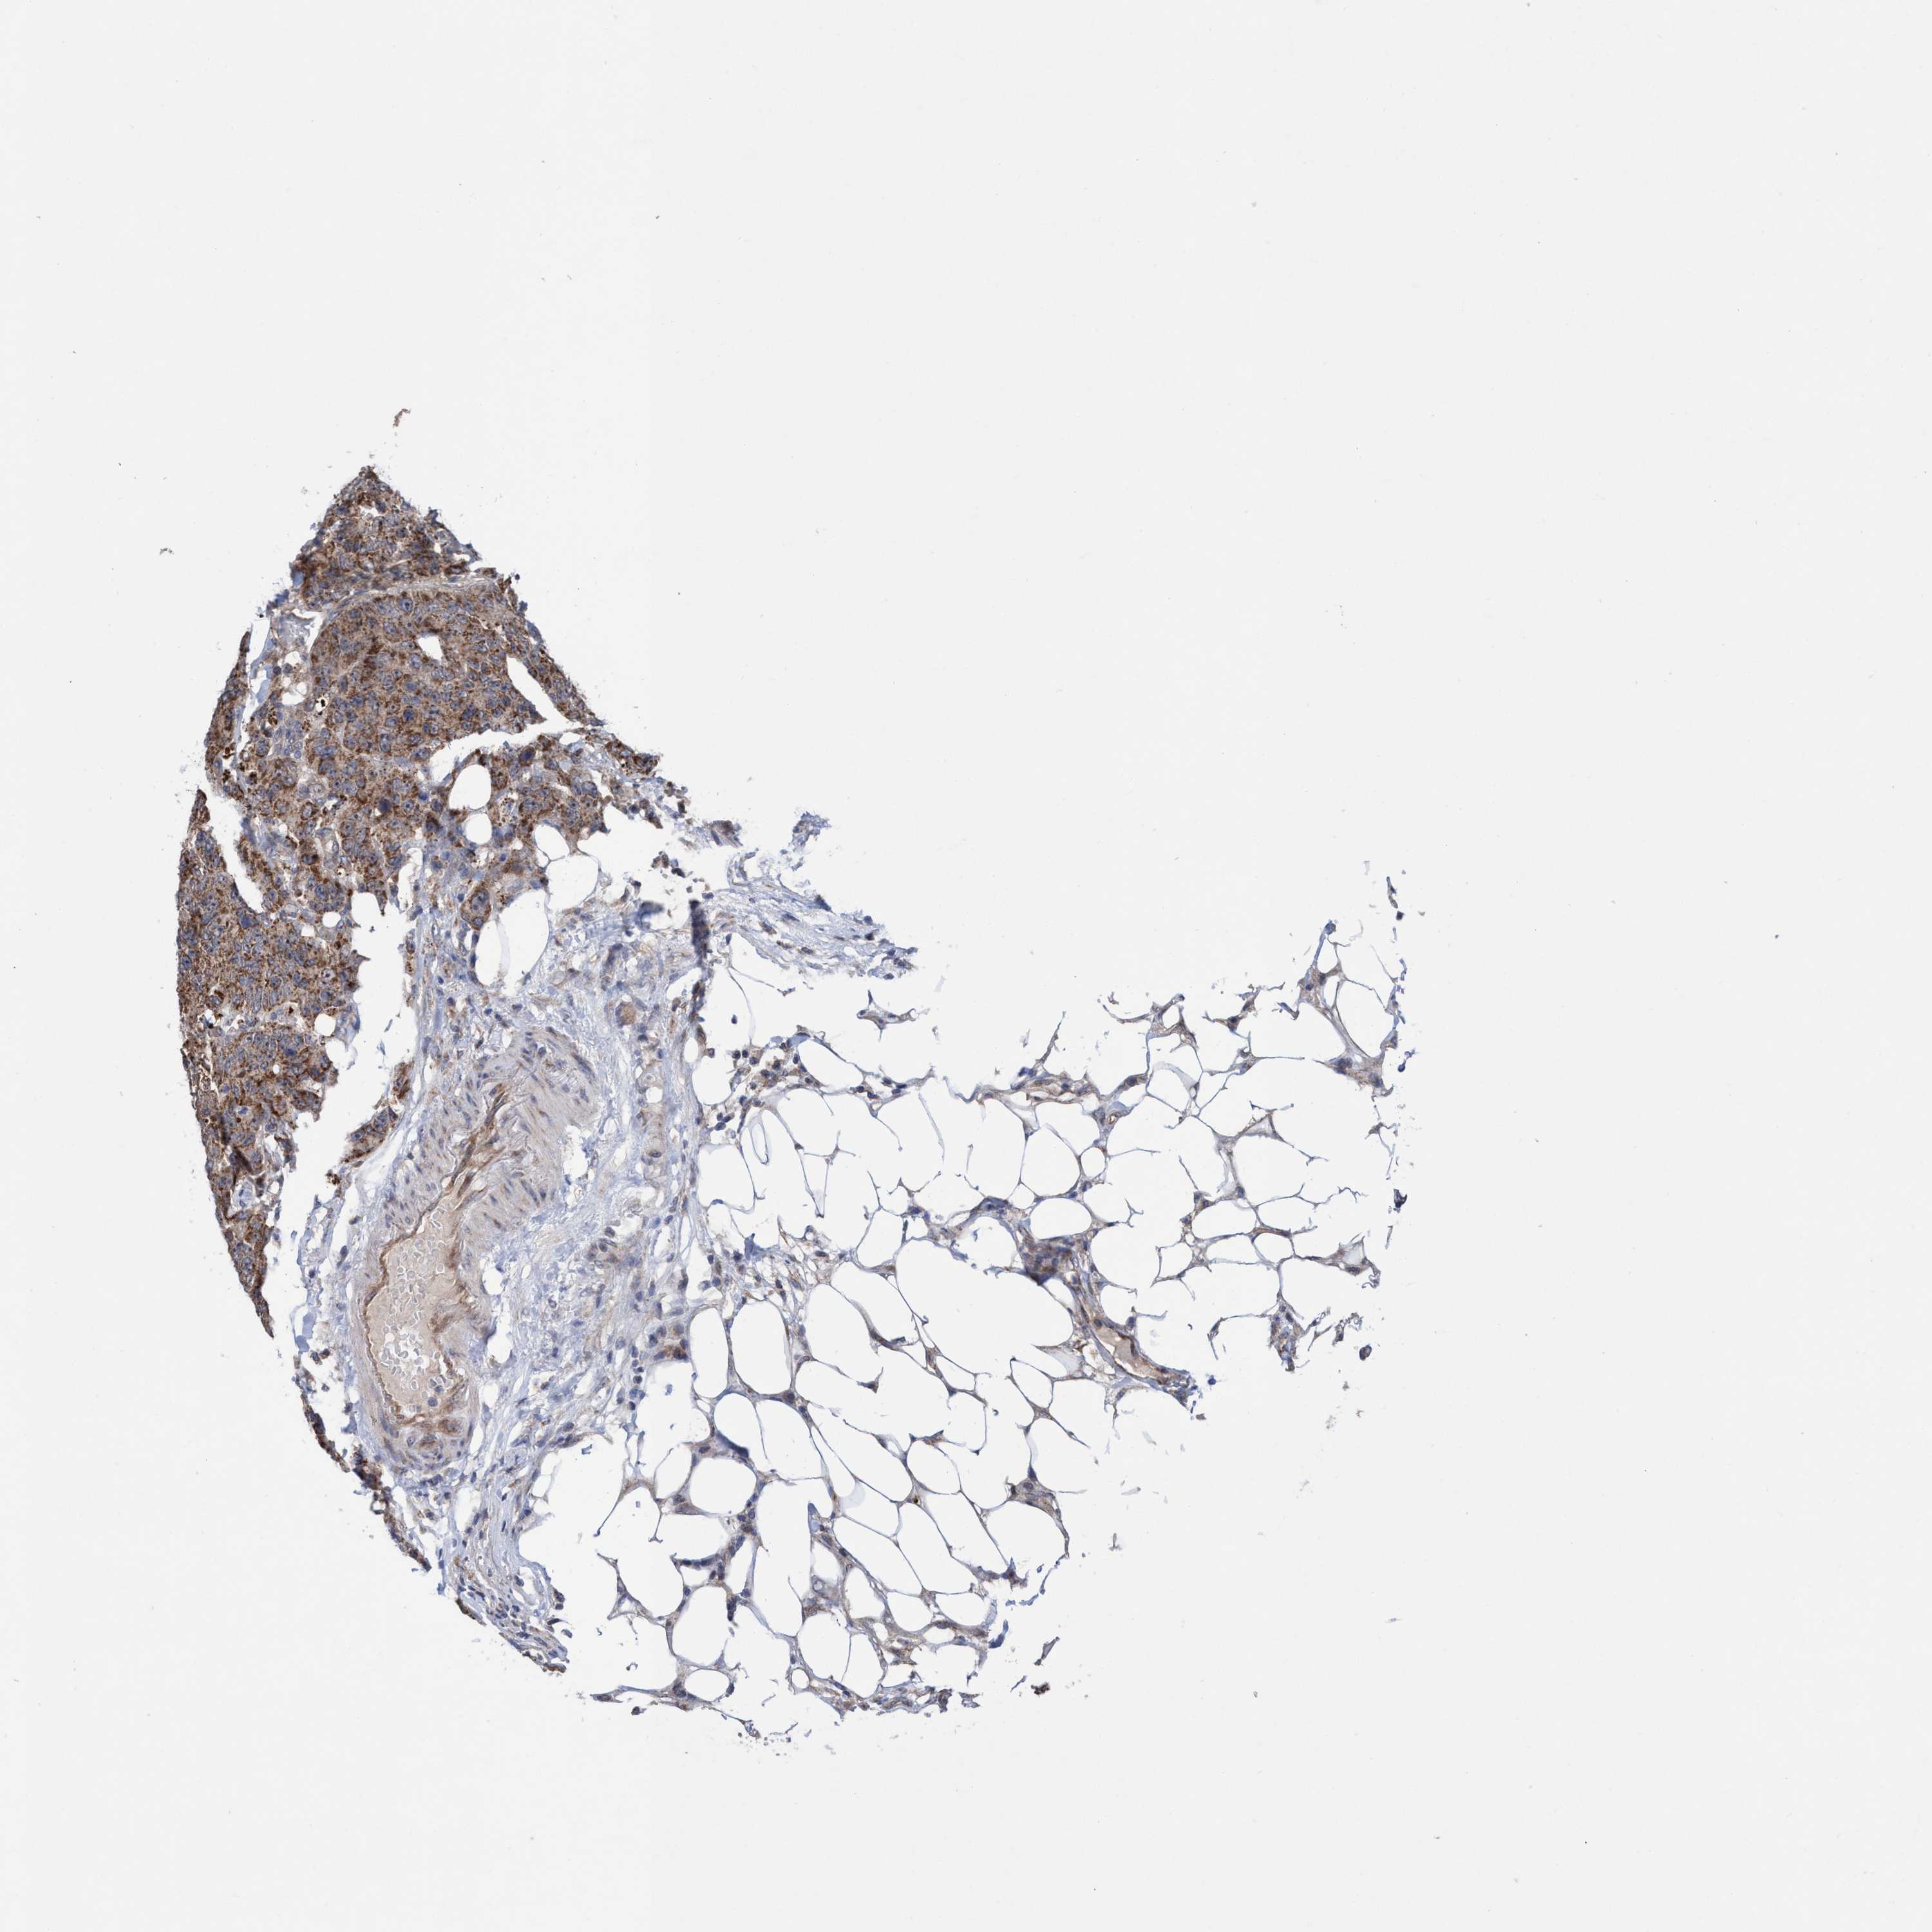

ANTIBODIES

AND

VALIDATION